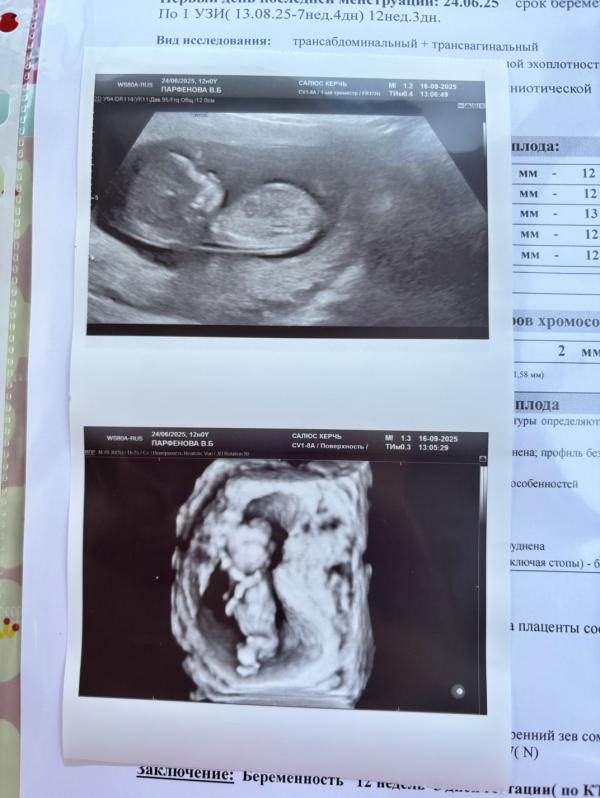

Результаты первого скрининга: УЗИ хорошее, ждем анализ крови

Первый скрининг прошли, по узи все хорошо, осталось дождаться кровь 🙏